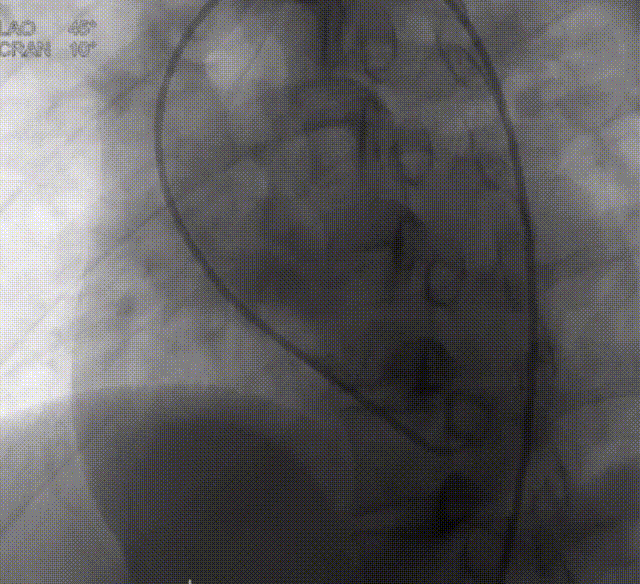

患者为28岁女性,术前超声示室间隔膜部有一约6 mm的室间隔缺损(膜周型),距三尖瓣5 mm、距主动脉瓣3 mm,室水平左向右分流,过隔流速5.3 m/s。VSD封堵术中术者在X线指导下顺利建立室间隔封堵工作路径后,经造影进一步评估VSD大小与形态,并沿鞘管输送一枚腰部直径10 mm的MemoSorb®全降解封堵器至室间隔缺损处。

造影评估室间隔缺损形态大小

后在TTE指导下,术者按照标准操作流程先释放封堵器左盘,牵拉成型线,使封堵器左盘由纺锤形变成“圆盘形”;后释放右盘,经二次成型,使封堵器骑跨缺损两侧,紧贴室间隔,锁定成型线。

上:左盘释放成型;下:右盘释放成型、双盘骑跨缺损两侧

经牵拉测试,封堵器位置形态稳定,对瓣膜功能无影响,故完全释放封堵器。

复查超声及造影提示封堵器位置形态稳定,无残余分流,手术圆满成功!

完全释放封堵器